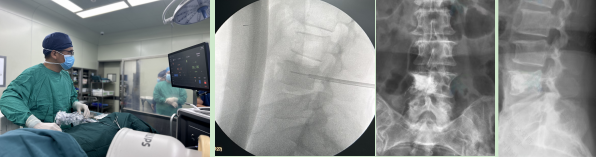

针对这样的问题,韩学哲、边卫国教授团队前期做了反复论证,积累了丰富的治疗经验,在保障患者安全,避免神经损伤的前提下成功实施手术。手术当日,在麻醉手术部的配合下,苏薇医生实施术中神经电生理监测,韩学哲、边卫国教授通过术中反复透视定位,建立工作通道,先对病变椎体进行-196℃「冰」消融,持续约 10 分钟,再快速升温至 80℃「热」消融,持续约 5 分钟,对椎体内肿瘤组织进行充分灭活,然后将骨水泥逐渐注入椎体内。术后即刻患者疼痛感明显缓解,疼痛评分下降至 2 分,并于当日下地活动。

胸 12 转移瘤患者术前、术中影像学检查、神经电生理监测及消融过程腰椎转移瘤患者为 60 岁女性,肺腺癌骨转移,腰背部疼痛有接近一月,直不起腰,不敢翻身,疼痛剧烈,疼痛评分 8 分,磁共振成像显示腰 4 椎体转移瘤。为解决患者的疼痛症状,团队决定实施复合式冷热消融、椎体成形手术。经过麻醉手术部的大力配合,顺利地完成了「冷」与「热」消融、椎体成形手术,术后患者双下肢功能正常,腰背部疼痛得到明显改善,疼痛评分降至 2 分。